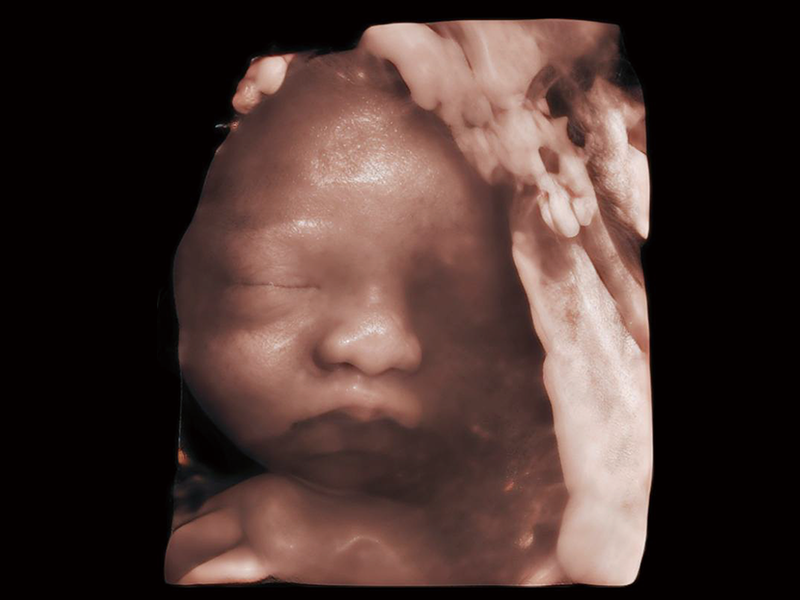

夢(mèng)溪?P80以“關(guān)愛(ài)女性”為基石,提供全方位的解決方案,量身定制以滿(mǎn)足女性的健康需求,涵蓋婦科、生殖健康檢查、產(chǎn)前篩查及產(chǎn)后康復(fù)等領(lǐng)域。

通過(guò)工作流協(xié)議、遠(yuǎn)程訪(fǎng)問(wèn)、自動(dòng)探頭激活和人體工程學(xué)優(yōu)化設(shè)計(jì)等功能,旨在提高臨床工作效率